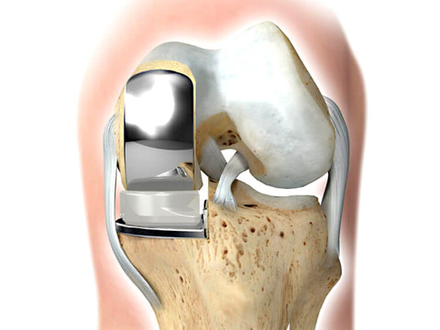

Эндопротезирование коленного сустава

Эндопротезирование — это открытая операция, при которой производится замена поврежденного коленного сустава на современный искусственный имплант.

Современные эндопротезы

Современные типы эндопротезов учитывают сложную биомеханику коленного сустава и максимально точно воспроизводят естественные движения.

Здоровый коленный сустав стабилизируется связками. В зависимости от клинической ситуации:

· некоторые импланты позволяют сохранить собственные связки пациента

· другие полностью берут на себя их функцию

Это обеспечивает стабильность, физиологичность движений и долговечность результата.